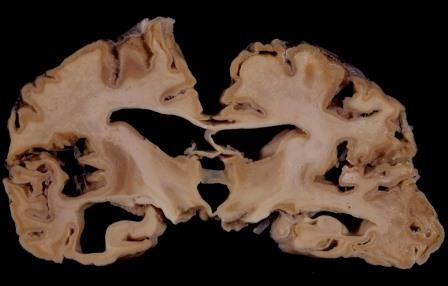

Cerebro dañado por los priones de la enfermedad de las vacas locas o síndrome de Creutzfeldt Jakob